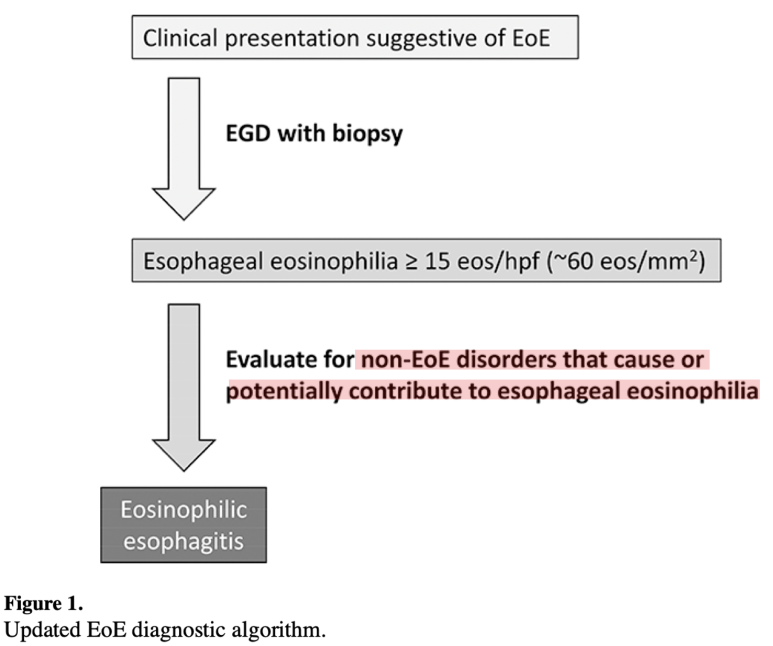

조직검사소견은 호산구가 H PF당 15개 이상 검출되는 것이 가장 중요하며, ECM 공간이 더욱 증가하고 basal zone hyperplasia가 동반되는 특징을 가지고 있습니다.

조직검사는 유럽의 경우 6개소를 시행할 것을 권고하고, 미국의 경우 2-4개의 promixal, distalesophagus에서 시행할 것을 권고하고 있습니다.진단 기준 상의 내용을 종합하여 호산구 식도염의 진단 기준을 확인하게 됩니다.먼저 전 세계에서 모여 만든 AGREE 컨퍼런스에서는 식도의 Dysfunction이 발생하는데 아토피 소인이 있고 내시경적으로 특징적인 소견이 있으며 조직학적으로 HPF당 15개의 호산구가 확인되어야 합니다. 이때 중요한 것은 호산구의 침착이 식도에만 국한되어야 하며 다른 2차적인 원인에 의해 식도 내 호산구가 증가하지 않는 것입니다. 즉, 다른 질환 없이 식도로만 호산구가 증가한다는 것을 의미합니다.

예를 들어 Achalaisa, 약물유발성식도염, 감염, GERD에 의해서도 호산구가 증가할 수 있으나 이러한 질환이 함께 발생할 경우에는 호산구식도염으로 진단할 수 없습니다.

즉, 식도 관련 증상이 있을 경우 내시경을 실시하고 조직검사에서 HPF당 15개 이상의 호산구가 있을 경우 식도 내에 호산구를 증가시키는 질환이 모두 제거된다는 가정 하에 호산구 식도염이라는 진단명을 붙일 수 있습니다.